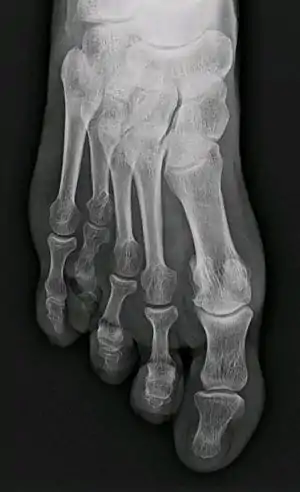

| X-ray of congenital brachymetatarsia involving fourth metatarsal bone | |